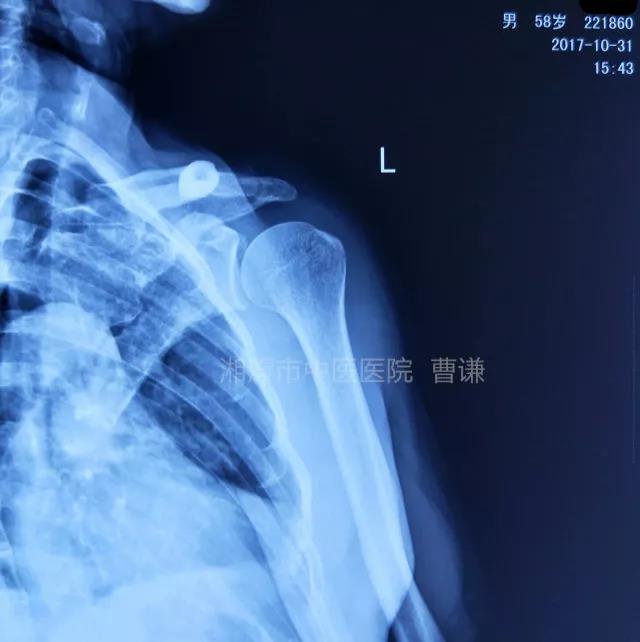

磁共振检查也完善了,还是报了个肩关节半脱位……影像科已经把坑挖好了……

接诊医生直接跳坑里了